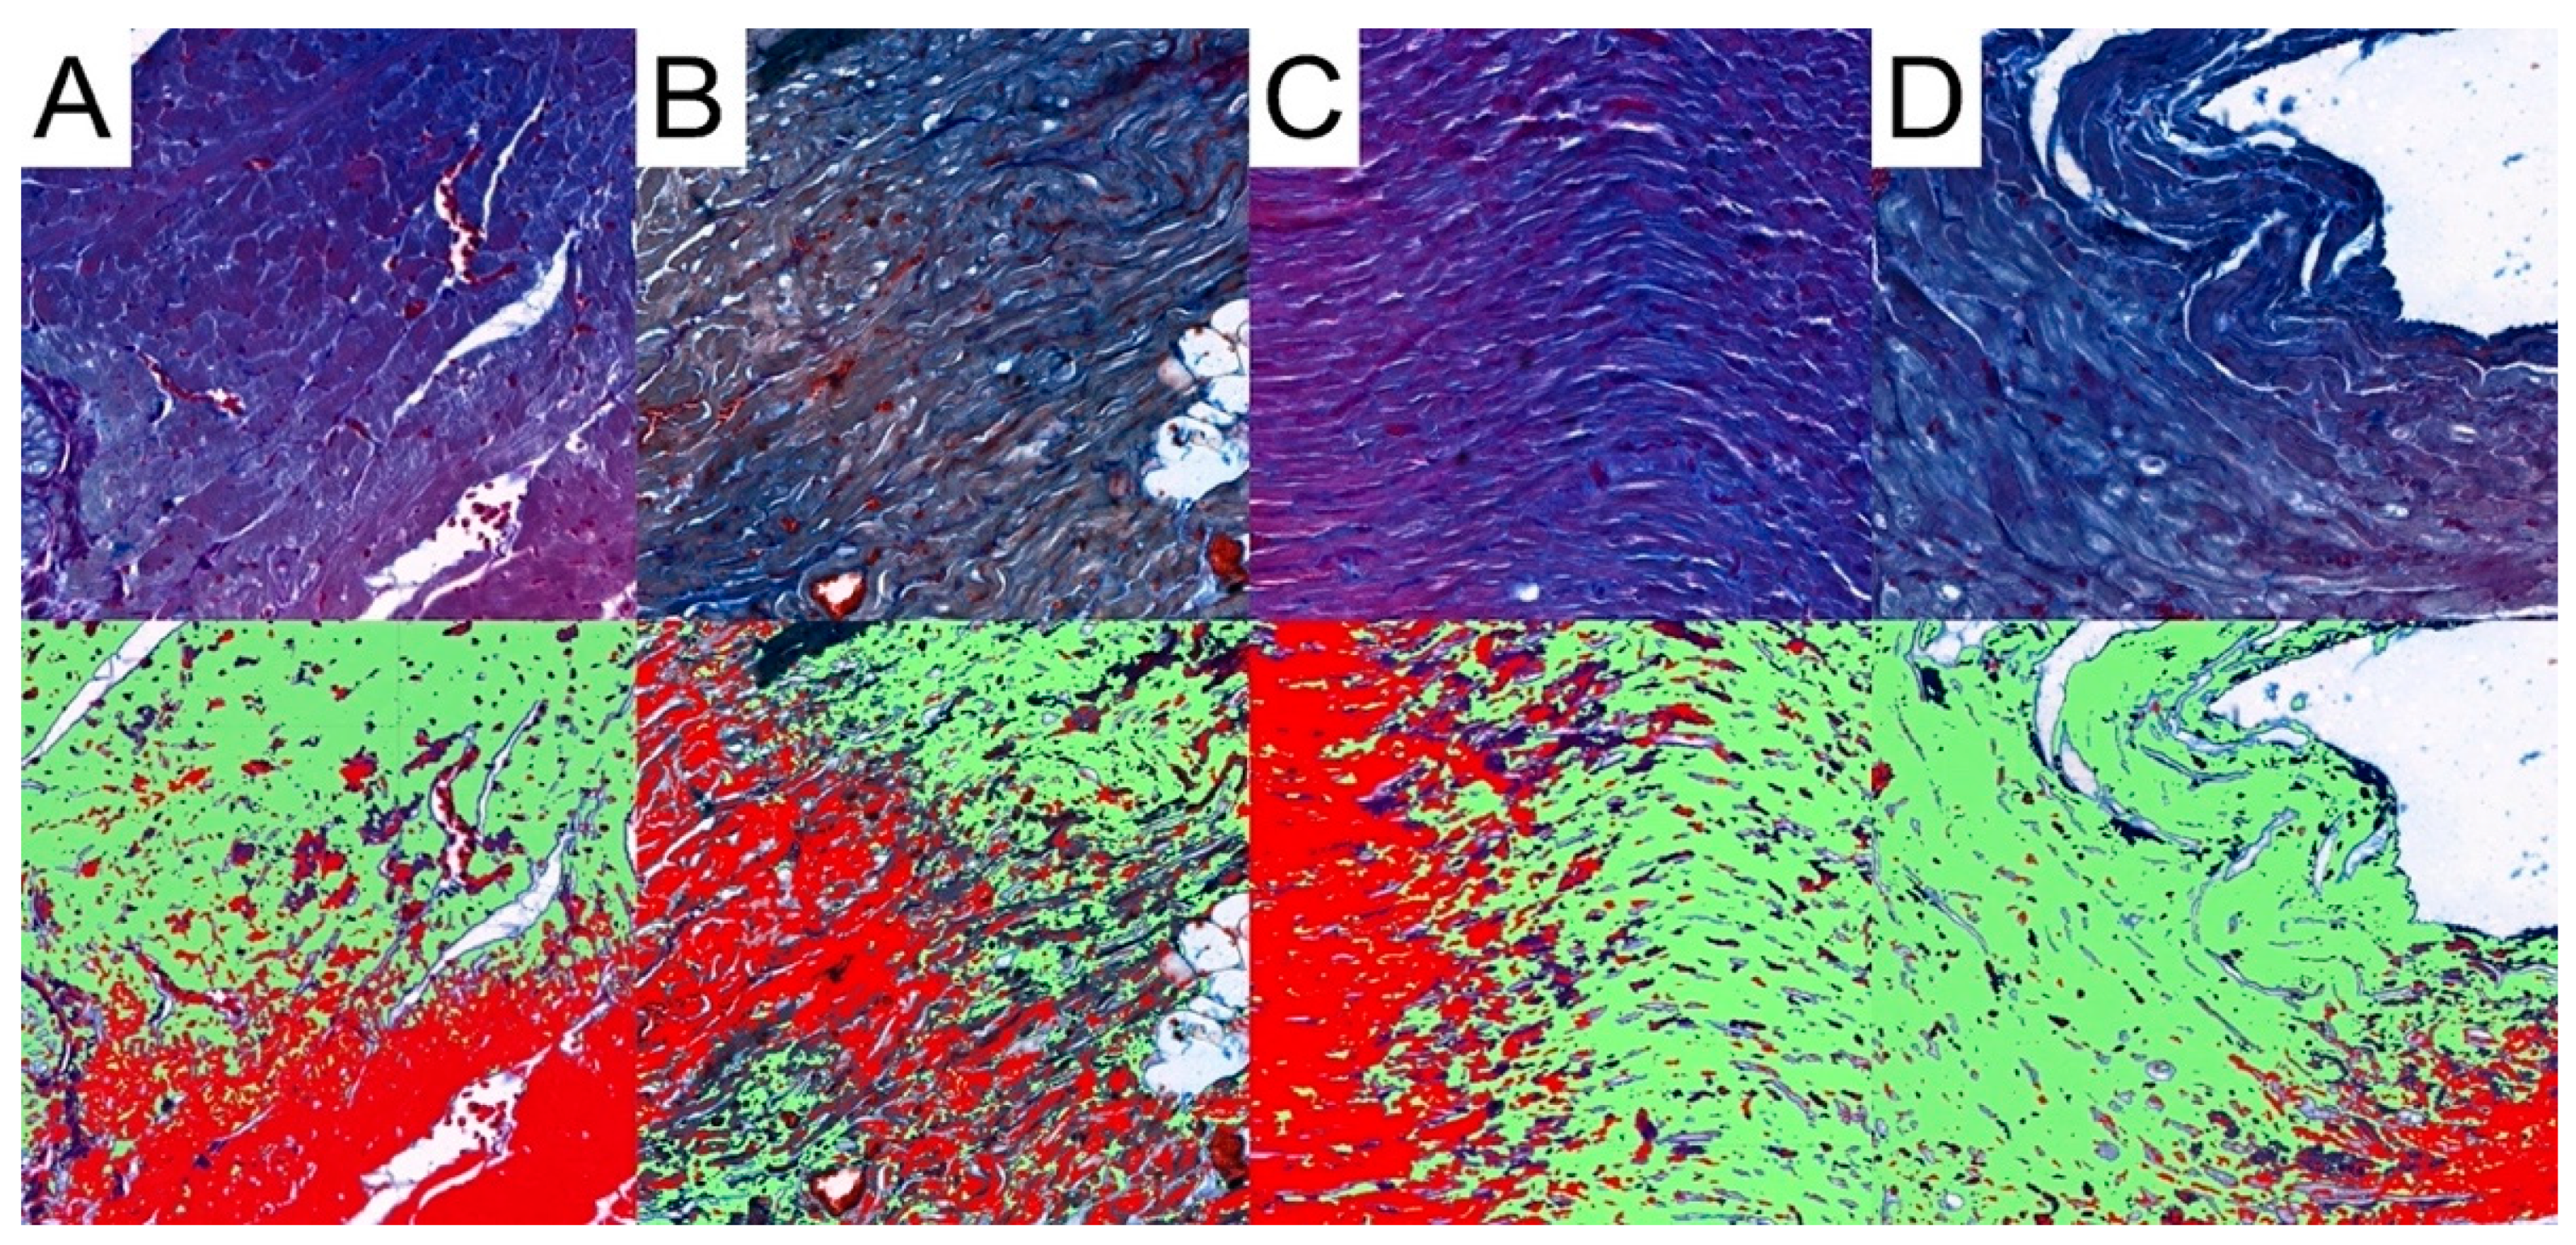

2.5. Collagen Fibers

3.4. Collagen Analysis

| Collagen area | 1.18 (1.12; 1.24) | 1.29 (1.105; 1.385) | 1.03 (0.94; 1.18) | 1.125 (0.77; 1.56) | 0.675 | CRG: 0.2555 TRG: 0.2592 MRG: 0.4645 | 0.1084 | 0.2305 | 0.2888 |